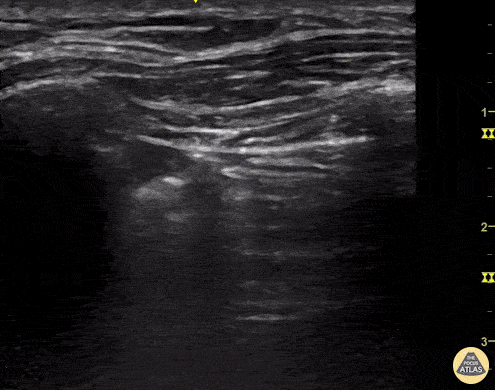

pneumothorax